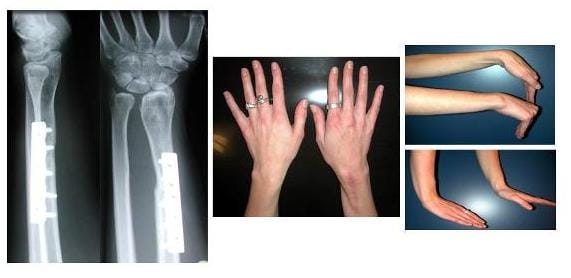

Das Wadenbein (Fibula) ist ein geeignetes Transplantat, um z.B. Knochengewebe der Speiche (Radius) oder des Oberarmes zu ersetzen.

Bilder eines bösartiger Knochentumor der Speiche wurde nach Entfernung durch einen Teil des Wadenbeins ersetzt

Ein bösartiger Knochentumor der Speiche (Radius) wurde nach Entfernung durch einen Teil des Wadenbeins (Fibula) ersetzt.

Links: Röntgenbild nach der Operation

Mitte und Rechts: klinisches Ergebnis

(Bilder: Prof. Dr. Ludger Bernd)